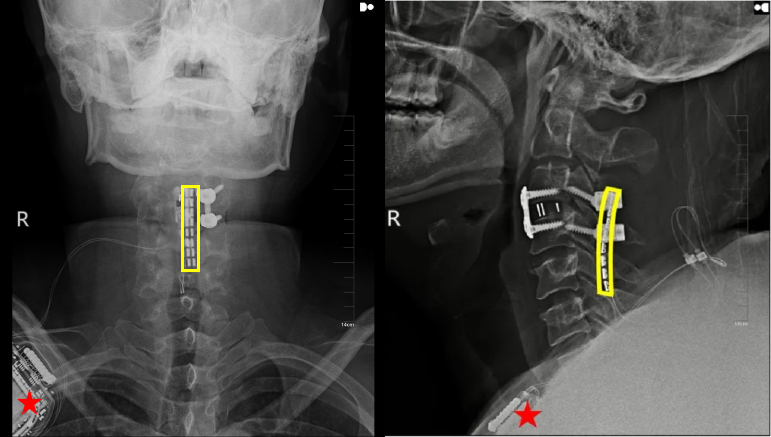

上圖:植入術后X線顯示,黃色方框為電極位置,星號為皮下脈沖發射器位置